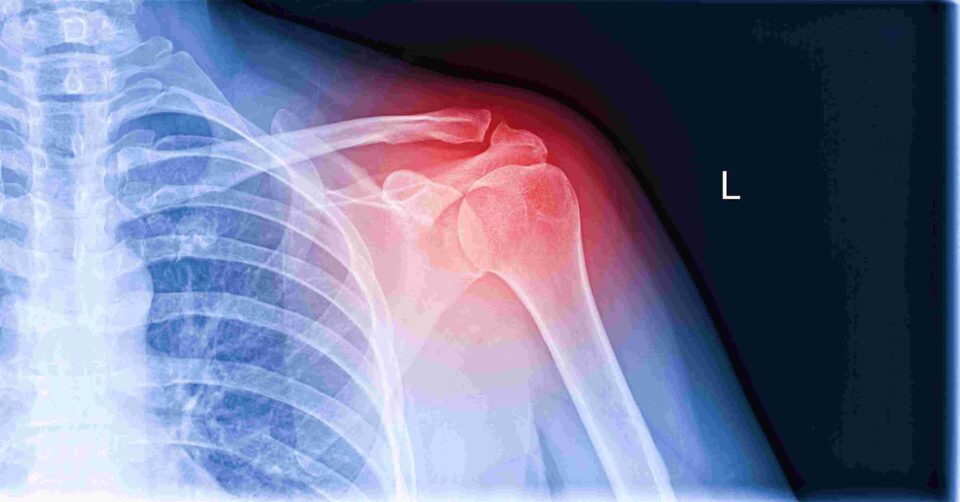

What You Need to Know About Rotator Cuff Surgery

Rotator cuff injuries can be debilitating. Not only are they painful, but they also affect your ability to perform everyday tasks. For many, rotator cuff surgery offers a path to recovery and a return to normal activities. At Texas Institute of Orthopedic Surgery & Sports Medicine, our rotator cuff repair specialists help patients from all over the DFW area understand their injuries and the procedures that can provide relief. Here’s what you need to know about rotator cuff surgery from our shoulder surgery experts.

We’ll begin with the basics—understanding the rotator cuff itself. It’s a group of muscles and tendons that stabilize the shoulder joint and allow for a wide range of movements. Rotator cuff strength and flexibility are crucial for activities like throwing, lifting, and even simple gestures like waving. Damage to the rotator cuff is all too common and can result from repetitive stress, sudden injuries, and age-related wear and tear. Be sure to meet with one of our providers if you have the following symptoms: